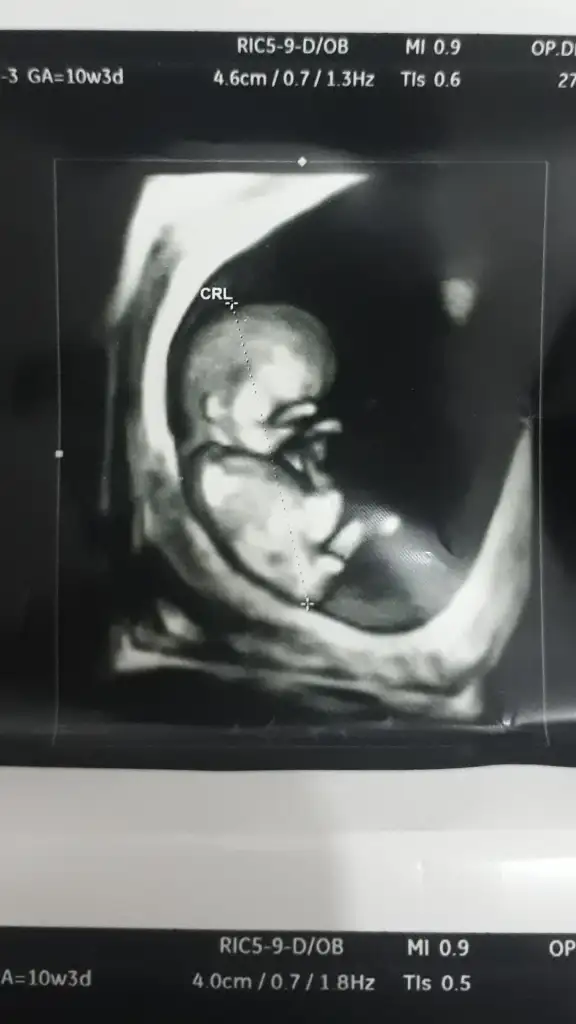

Şimdilik erkek yönünde ama en iyi 11 12 13 haftalar olmalıRica etsem bize de bakar mısınızburada 10+4

çok teşekkür ederim❤Şimdilik erkek yönünde ama en iyi 11 12 13 haftalar olmalı

Sanki erkek gibi